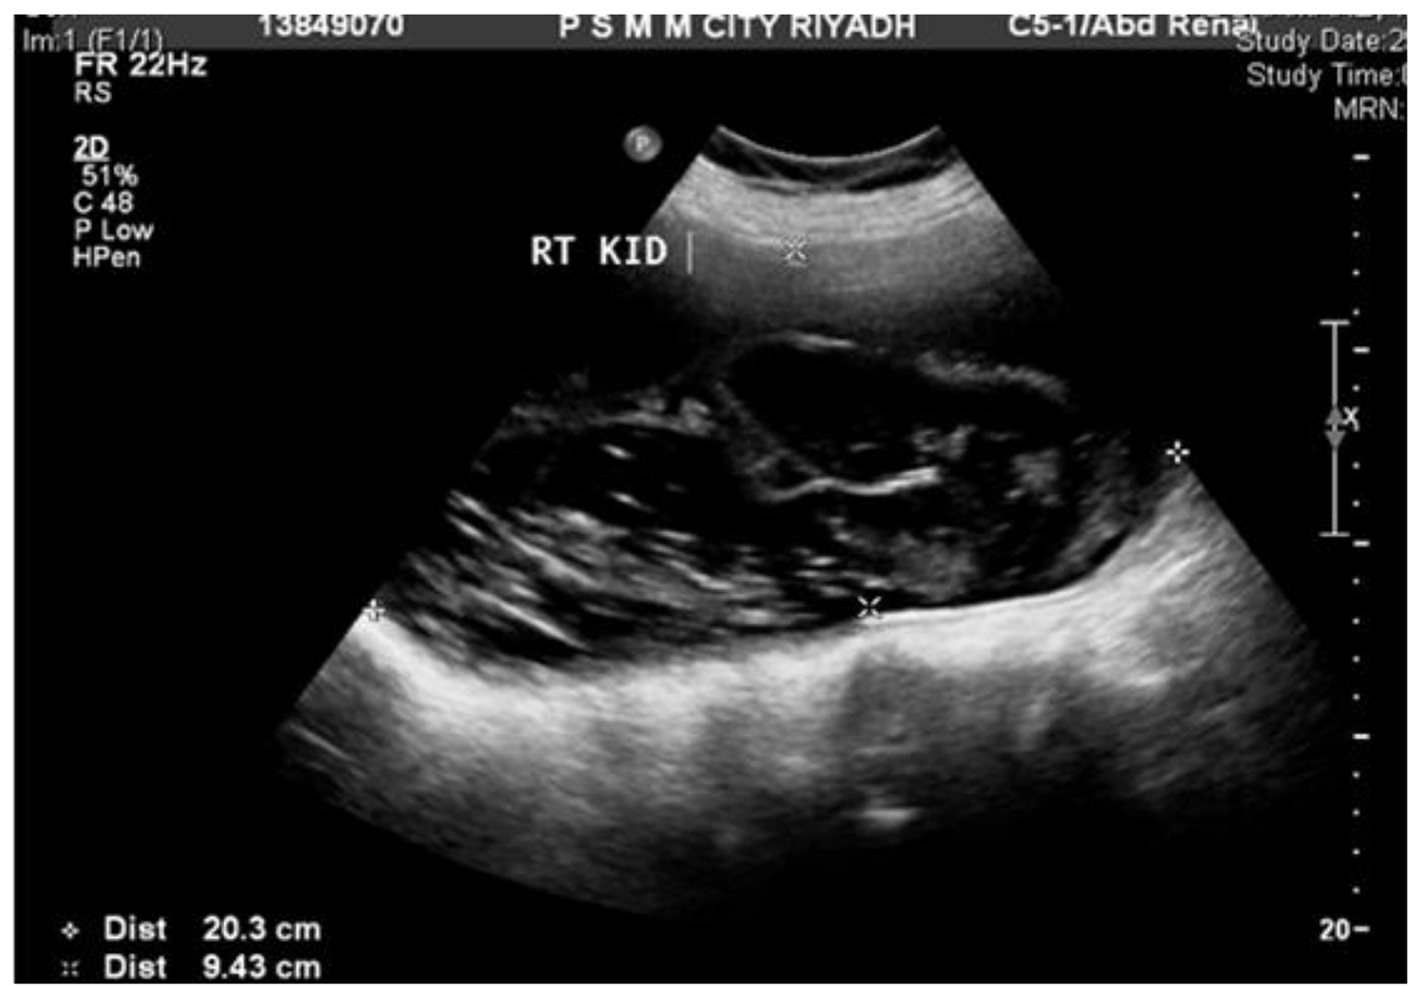

A 65-year-old woman with DM and hypertension was admitted to hospital with 8 years history of right lumbar pain. She used to live in the desert with strong history of contact with animals including dogs. She denied any urinary or other systemic symptoms. General examination was normal. Abdominal examination showed a 7 × 6 cm paraumbilical hernia. US abdomen showed a complex cystic structure measuring 20 × 9.4 cm occupying the right renal region that revealed multiple septations, coiled membranes and internal debris. Several internal small cysts are seen, features of which were consistent with hydatid cyst (Fig. 1, 2). Similarly, MRI disclosed a huge cystic lesion involving the upper and mid pole of the right kidney producing anterior displacement of the liver and pancreas with a thin T2 hypointense wall. There is a long smoothly outlined linear structure within the cyst, which includes multiple tiny cysts, likely representing an infolded ruptured wall of a hydatid cyst (Fig. 3). CT scan of the abdomen, chest and pelvis confirmed a giant hydatid cyst in the right kidney with no evidence of other cysts in the liver or the lungs (Fig. 4). The eosinophil count was normal both before and after surgery. Serum creatine remained normal despite a right kidney contributing only 5% of the renal function on DMSA scan. Urine and aspirate of cyst fluid was repeatedly negative for hydaturia. IHA serology for hydatid was also negative.

![]() Click for large image | Figure 2. US abdomen. |